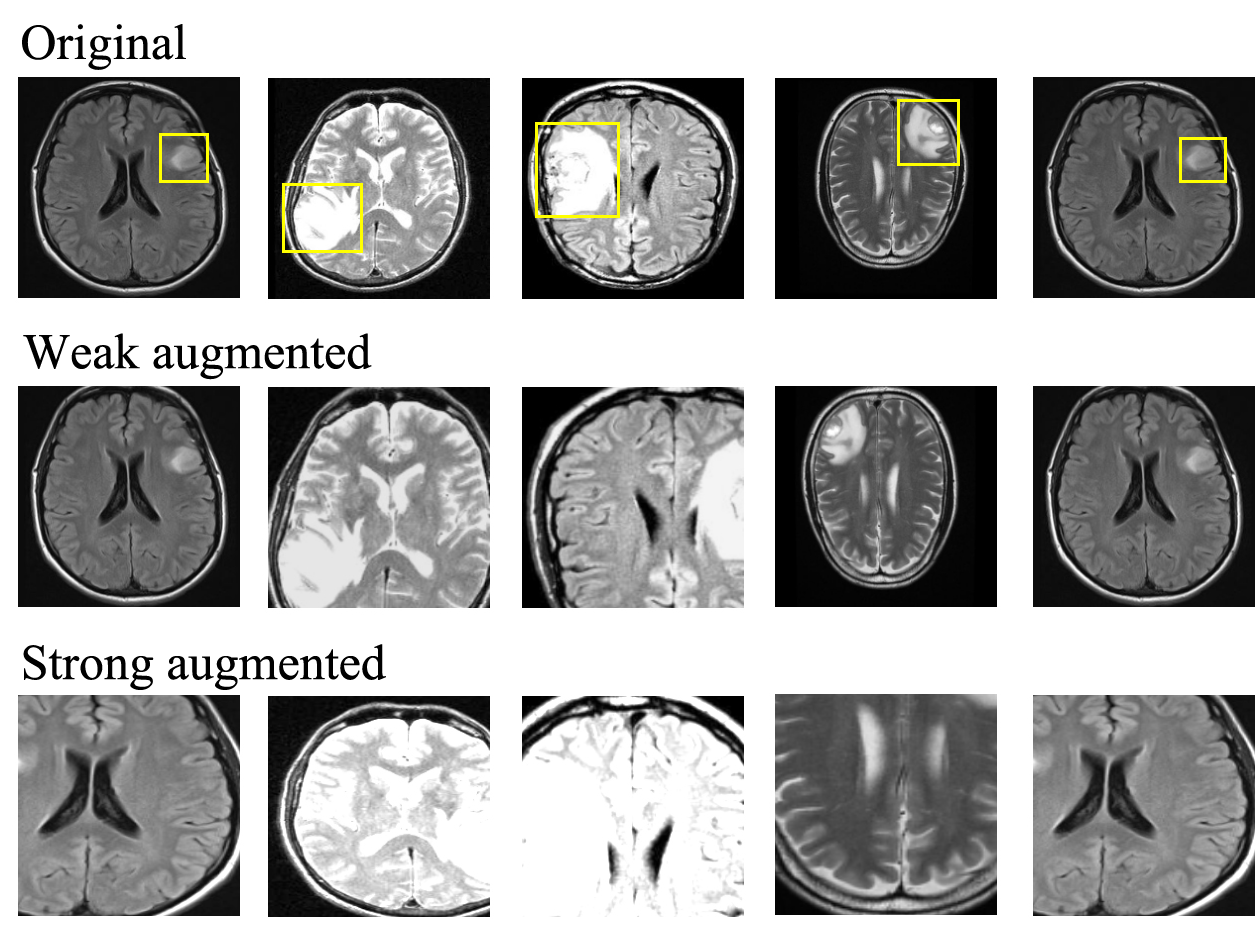

With the emergence of deep learning, self-supervised learning has been introduced as a new learning representation that does not rely on labels. Each sample is transformed into two different versions using strong and weak data augmentation processes, as shown in Fig. 1. Weak augmentation utilizes less aggressive transformation, such as applying random cropping, rotation, scaling, flipping, noise, and contrast to the image, whereas strong augmentation uses more aggressive transformation. The encoder model, which projects from high-dimensional to low-dimensional representation, is devised to distinguish them during training using contrastive loss [5]. Nevertheless, some scholars demonstrated that with the help of a small portion of the labels (in a semi-supervised learning manner), the encoder can obtain a better separability performance compared with the self-supervision version [6, 7]. Notably, the outcome of this representation learning is only an encoder network that is commonly used for downstream tasks, such as multi-class classification and BC. Using this technique, several semi-supervised classification tasks, particularly in multi-class classification (such as CIFAR, STL-10, and ImageNet), have been solved with remarkable and nearly similar results compared to the fully supervised setting, as demonstrated in the studies presented in [7, 8, 6]. However, these approaches rely on stochastic data augmentation techniques. Strong data augmentation can reduce or even omit important features, as shown in Fig. 1. In BC datasets, the positive and negative samples are commonly distinguished by an important feature, which can be relatively subtle and trivial in some cases, as shown in Fig. 1 1(a) and 1(c); thus, the feature can be removed while the images are augmented. Hence, transforming or removing this information can result in a misleading classification outcome because it can be detected in all negative samples